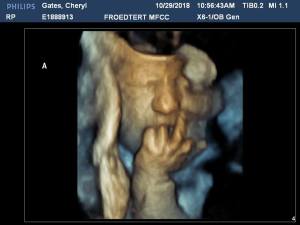

And one last parting shot – the only photo either baby would give us at their last scan. Typical. Right back at you kiddo.